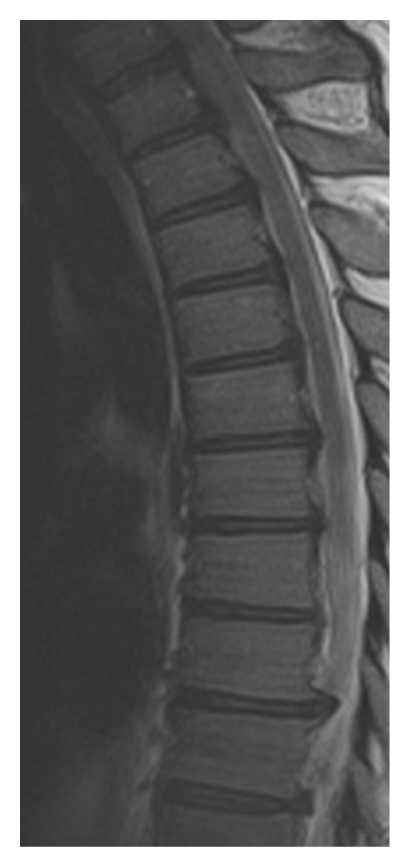

Adequate decompression of the spinal cord was confirmed by postoperative MRI (Figure 6).

(a)

(b)

(c)

(d)